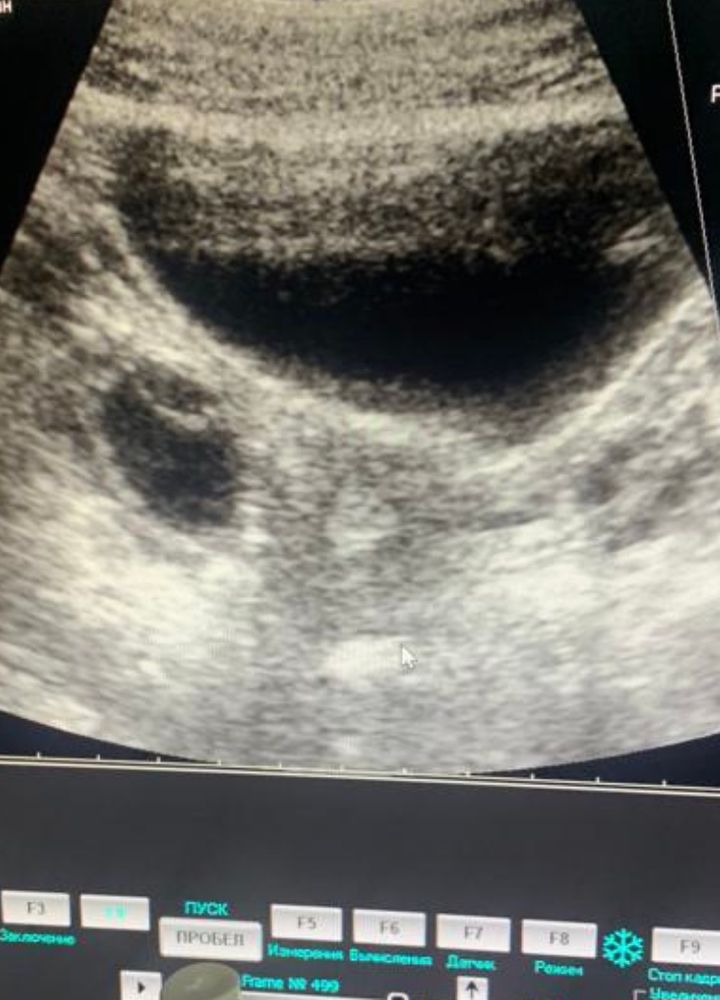

Киста с перегородкой

По идее, перегородка ничего не значит. Может быть фибриновый тяж, может слизистая так отвисает. Пока не вскрыть - не понятно. Лично я б не переживала. Столько всяких разных кист видела. Вот когда с взвесью или множественные тяжи - то тут ппц, плохо

Дашута, гинеколог на старом аппарате узи смотрел в среду,сказал,что ему все не нравится и отправил сдавать онкомаркеры,я сдала,переделала у другого узиста на новом аппарате ,он написал,что фолликулярные кисты. Одна с тонкой эхопозитивной перегородкой. У меня в дневнике есть пост,там фото,и,что в каждом яичнике по 3,4 фолликула. Brads2. Я конечно ужасно боюсь результатов. Почему такой разгон у них. Надо переделывать мрт?второй узист вообще сказал,забыть и ходить дальше и на узи через год

Здравствуйте. Как ваша ситуация разрешилась?у меня какая-то тоже полная попа по узи..перегородка в образовании,на каждом яичнике по кисте вроде,отправили на онкомаркеры сдавать..жду